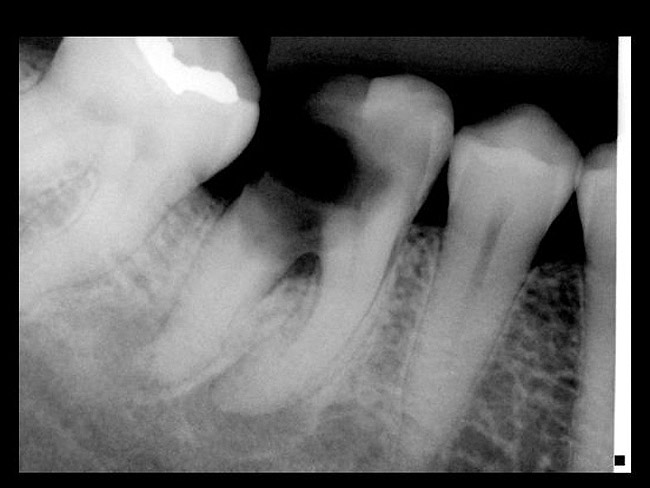

Bone loss is an indicator of past periodontal disease as well. Gustavo et al have established a guideline for percentage of bone loss relative to long-term prognosis.15 Bone loss percentage calculation was based on the total length of the root from the cemento-enamel junction to the apex minus approximately 2 mm (biologic width) to the length of the root supporting the alveolar bone. They divided bone loss into three categories < 30% (predictable),16,17 30% to 65% yellow (caution),18-20 and > 65% (consider extraction).13 This does not mean that all teeth with greater than 65% of bone loss need to be extracted; rather, teeth in this category as a whole have a poorer prognosis than teeth with less than 65% bone loss.

Bone defect morphology plays an important role in the predictability of tooth retention as well. Horizontal defects are unpredictable to guided tissue regeneration attempts (Figure 8). Narrow vertical defects respond more favorably to regeneration attempts (Figure 9).21